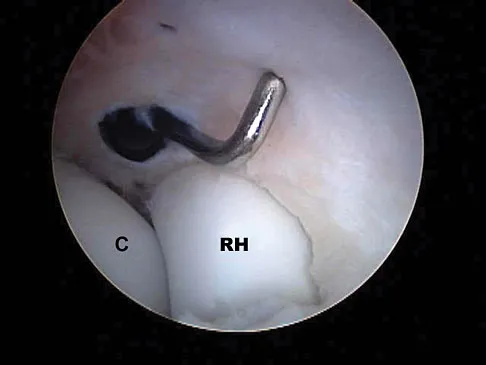

What neurovascular structure is in closest proximity to the probe in the arthroscopic view of the elbow shown in Figure 50?

Explanation